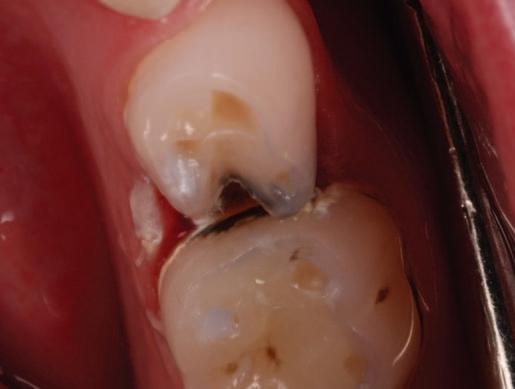

Create a flipbook

Issuu converts static files into: digital portfolios, online yearbooks, online catalogs, digital photo albums and more. Sign up and create your flipbook.